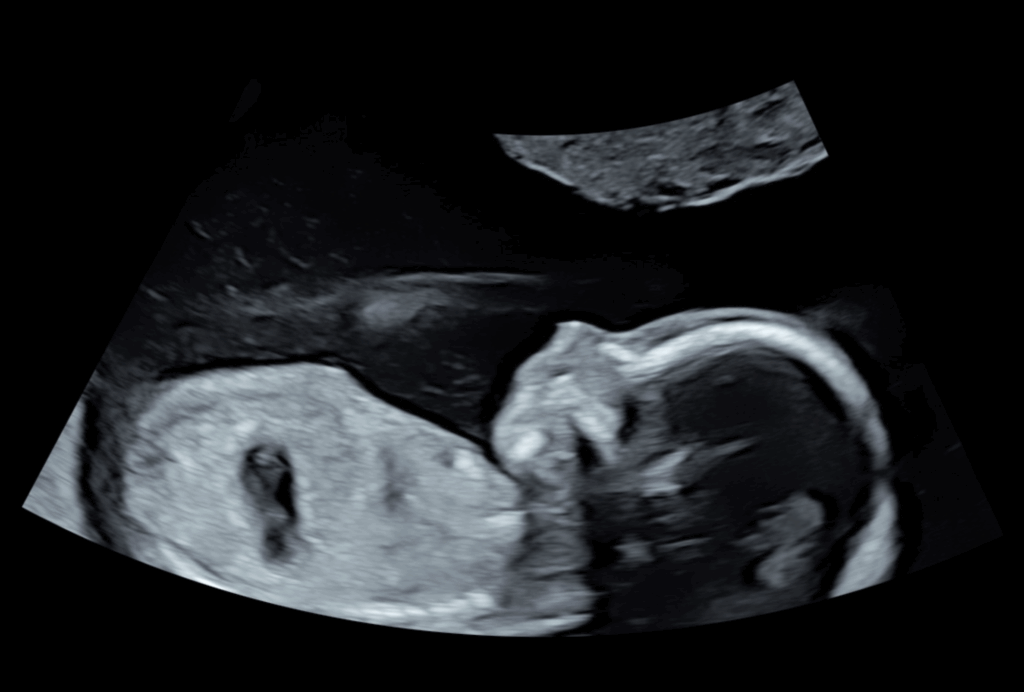

• Erste Ultraschalluntersuchung (Herzaktion ab 6. Schwangerschaftswoche)

Ultraschall

Zusätzliche Ultraschalluntersuchungen als Selbstzahlerleistung

• Vitalitätskontrolle des Kindes 24,76€

• Ultraschalluntersuchung des Kindes zu Vitalität und Wachstum 37,14€

Diese Ultraschalluntersuchungen werden im Rahmen der Mutterschaftsrichtlinien von Facharztpraxen für Frauenheilkunde und Geburtshilfe angeboten.

• ca. 10. Schwangerschaftswoche

• ca. 20. Schwangerschaftswoche (Organscreening)

• ca. 30. Schwangerschaftswoche